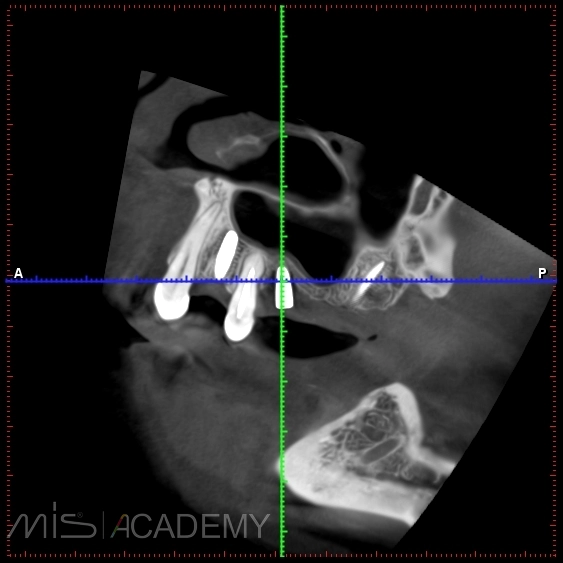

— На первом этапе было установлено три имплантата в области 2.4, 2.6 (закрытый синус-лифтинг) и 2.7 (птеригоидная установка).

— Через 3 месяца было обнаружено отторжение имплантата в области 2.6, потеря костной ткани в области шейки. Для устранения данного осложнения, во время удаления имплантата 2.6 был фиксирован костный блок, взятый из бугра верхней челюсти справа.

— Одномоментная переустановка имплантата в области 2.6.

— Установлен connect абатмент в области 2.4 и прямой MU в области 2.6.